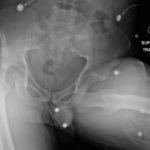

The initial radiograph of the pelvis revealed bilateral hip dislocations. Small bony fragments were noted in the right hip joint, suggestive of an underlying fracture. The sacroiliac joints and the pelvic ring were intact. In the emergency department, bilateral hip reductions were performed using the Captain Morgan technique.1 The post-reduction film showed reduction of the bilateral hip dislocations with extensive comminuted and displaced fractures of the right and left acetabula.